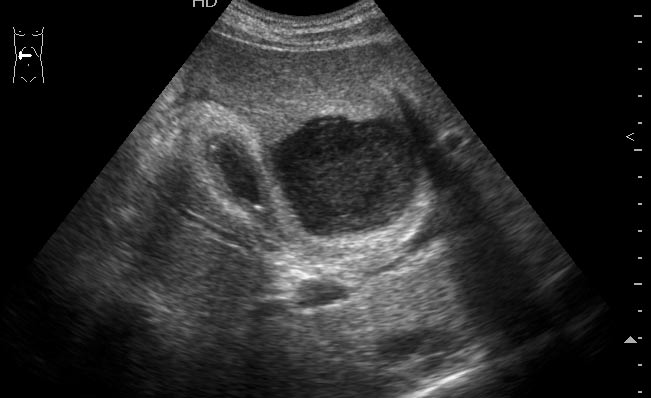

Мужчина средних лет, поступил в хирургическое отделение с диагнозом хронический панкреатит, обострение.

При УЗИ обследовании выявлена такая штука (см ниже). Несколько последних дней температура 39 С

УЗИ: Абсцесс печени

Печень?, абсцесccc>>>>>дренаж

Да.Брехт писал(а):Печень?, абсцесccc>>>>>дренаж

Откуда взялся,не из соседнего ли ж.пузыря,который почти спавшийся и с очень толстыми и расслоенными стенками

Нет, пузырь здесь непричем - он практически не измнён.besliu писал(а):Откуда взялся,не из соседнего ли ж.пузыря,который почти спавшийся и с очень толстыми и расслоенными стенками

Хронический панкреатит.